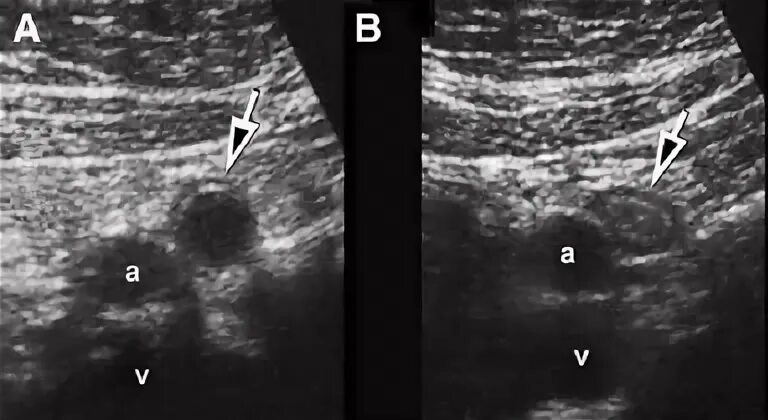

Аппендицит на узи можно ли